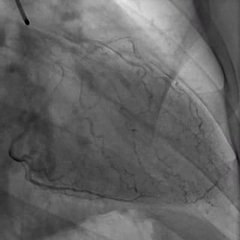

Angiography or arteriography is a medical imaging technique used to the inside, or lumen, of blood vessels and organs of the body, with particular interest in the arteries, veins and the heart chambers.